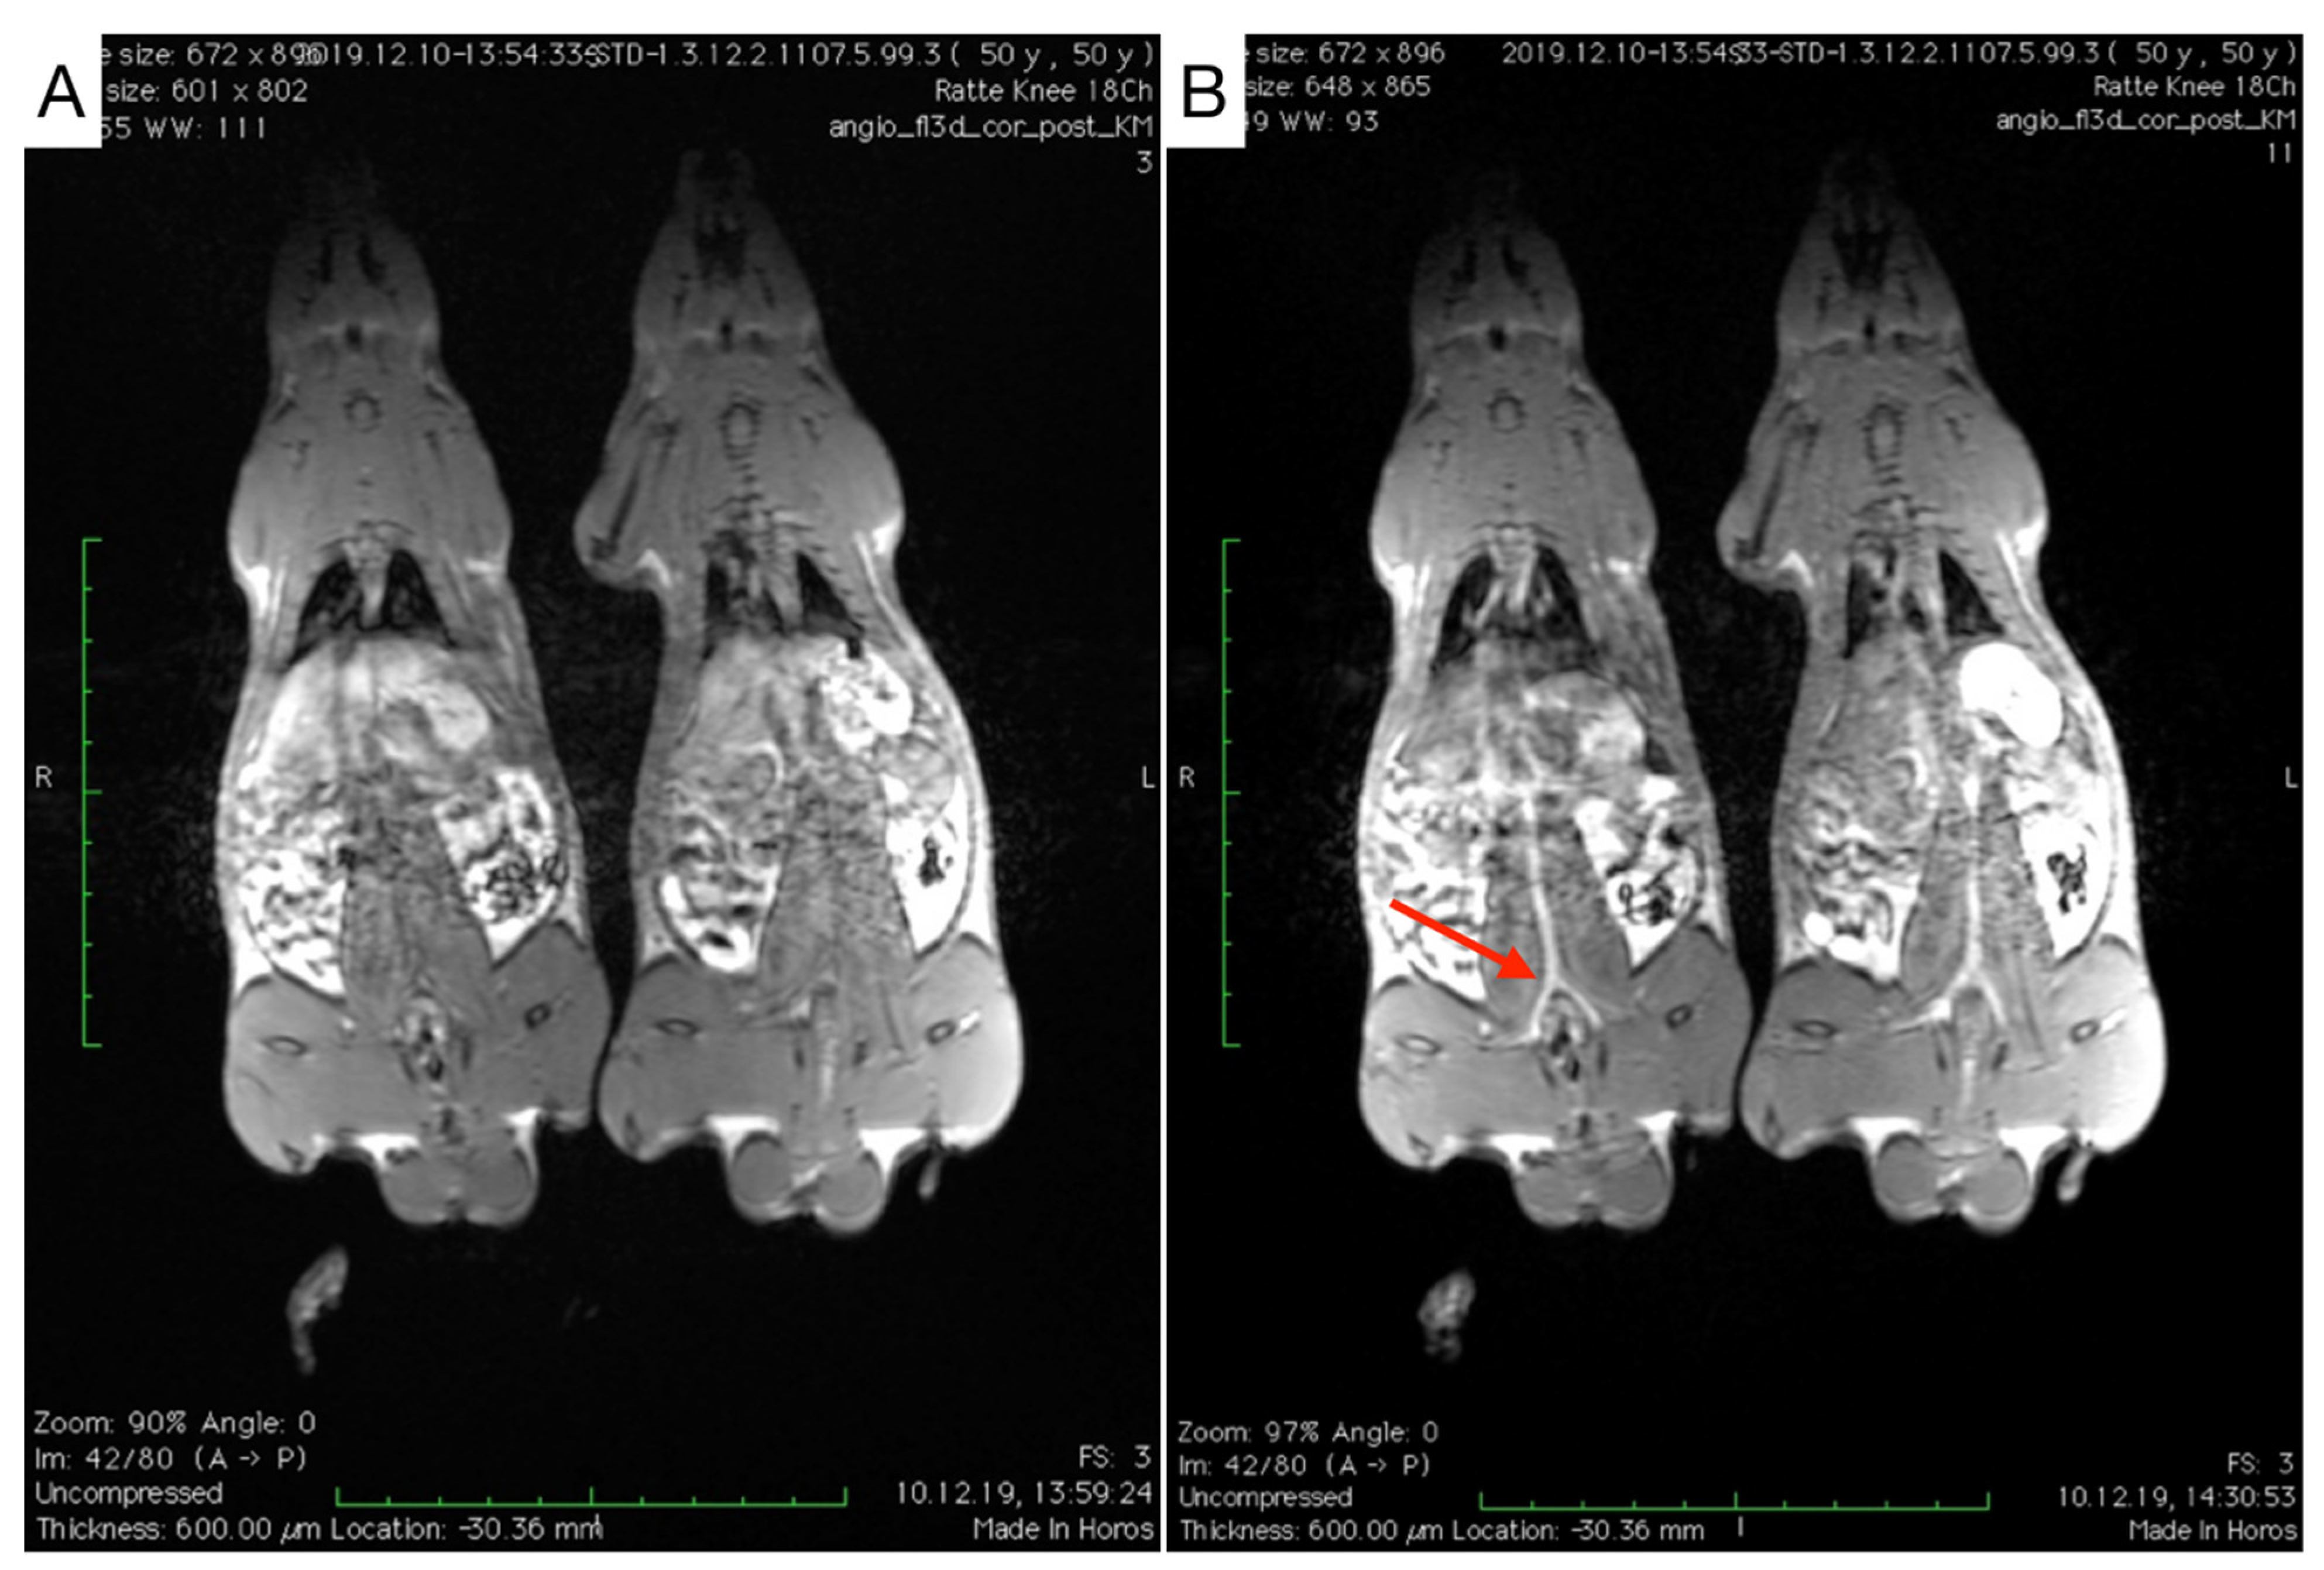

3.2. Animal Blood Half-Life Determination Using MRI

3.2.1. Blood Half-Life Determination of MCP-PEG10K

3.2.2. Blood Half-Life Determination of MCP-PEG10K2